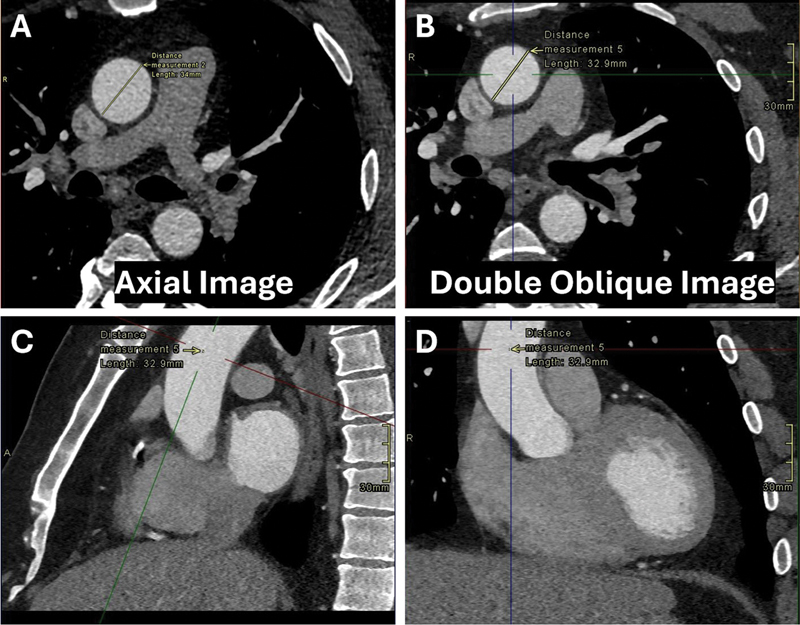

The purpose of the study was to compare axial measurements of the ascending thoracic aorta on gated CT study studies with double oblique measurements and calculate the divergence between orthogonal axial and double oblique diameters of the tubular ascending aorta.Retrospective measurements of axial and double oblique diameters were obtained in 153 consecutive patients.On average, the axial dimension exceeded the double oblique measurement.Our study endorsed the subtraction of 0.58 mm from the axial diameter in order to obtain the double oblique measurement.

本研究的目的是比较门控CT对胸升主动脉的轴向测量和双斜向测量,并计算管状升主动脉的正交轴向直径和双斜向直径之间的差异。对153例连续患者进行了轴向和双斜向直径的回顾性测量。平均而言,轴向尺寸超过双斜向测量。我们的研究支持从轴向直径减去0.58 mm以获得双斜向测量。